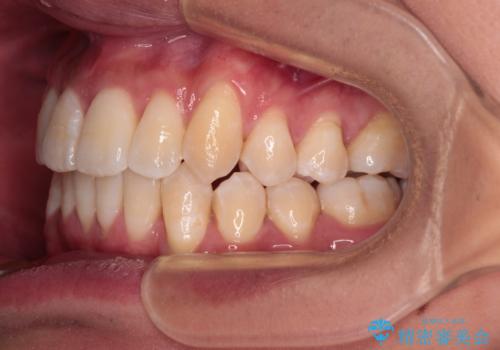

- 八重歯と飛び出している前歯を気にして来院された患者様です。

歯列としてはインビザラインでもワイヤー矯正でも対応できるものでしたが、上顎の八重歯や下顎小臼歯の捻転といったインビザラインでは時間のかかってしまう歯列不正が認められたため、補助装置やワイヤー矯正を治療当初に使用することで、インビザラインによる治療をスムーズに行えるように計画しました。